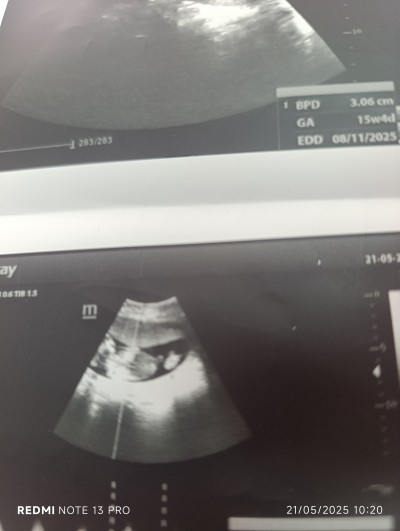

cinsiyet tahmini alabilir miyim

Gebelik haftası

15

Kız gibi canım

Nasil anladn canm

Kese şeklinden ve çıkıntıdan